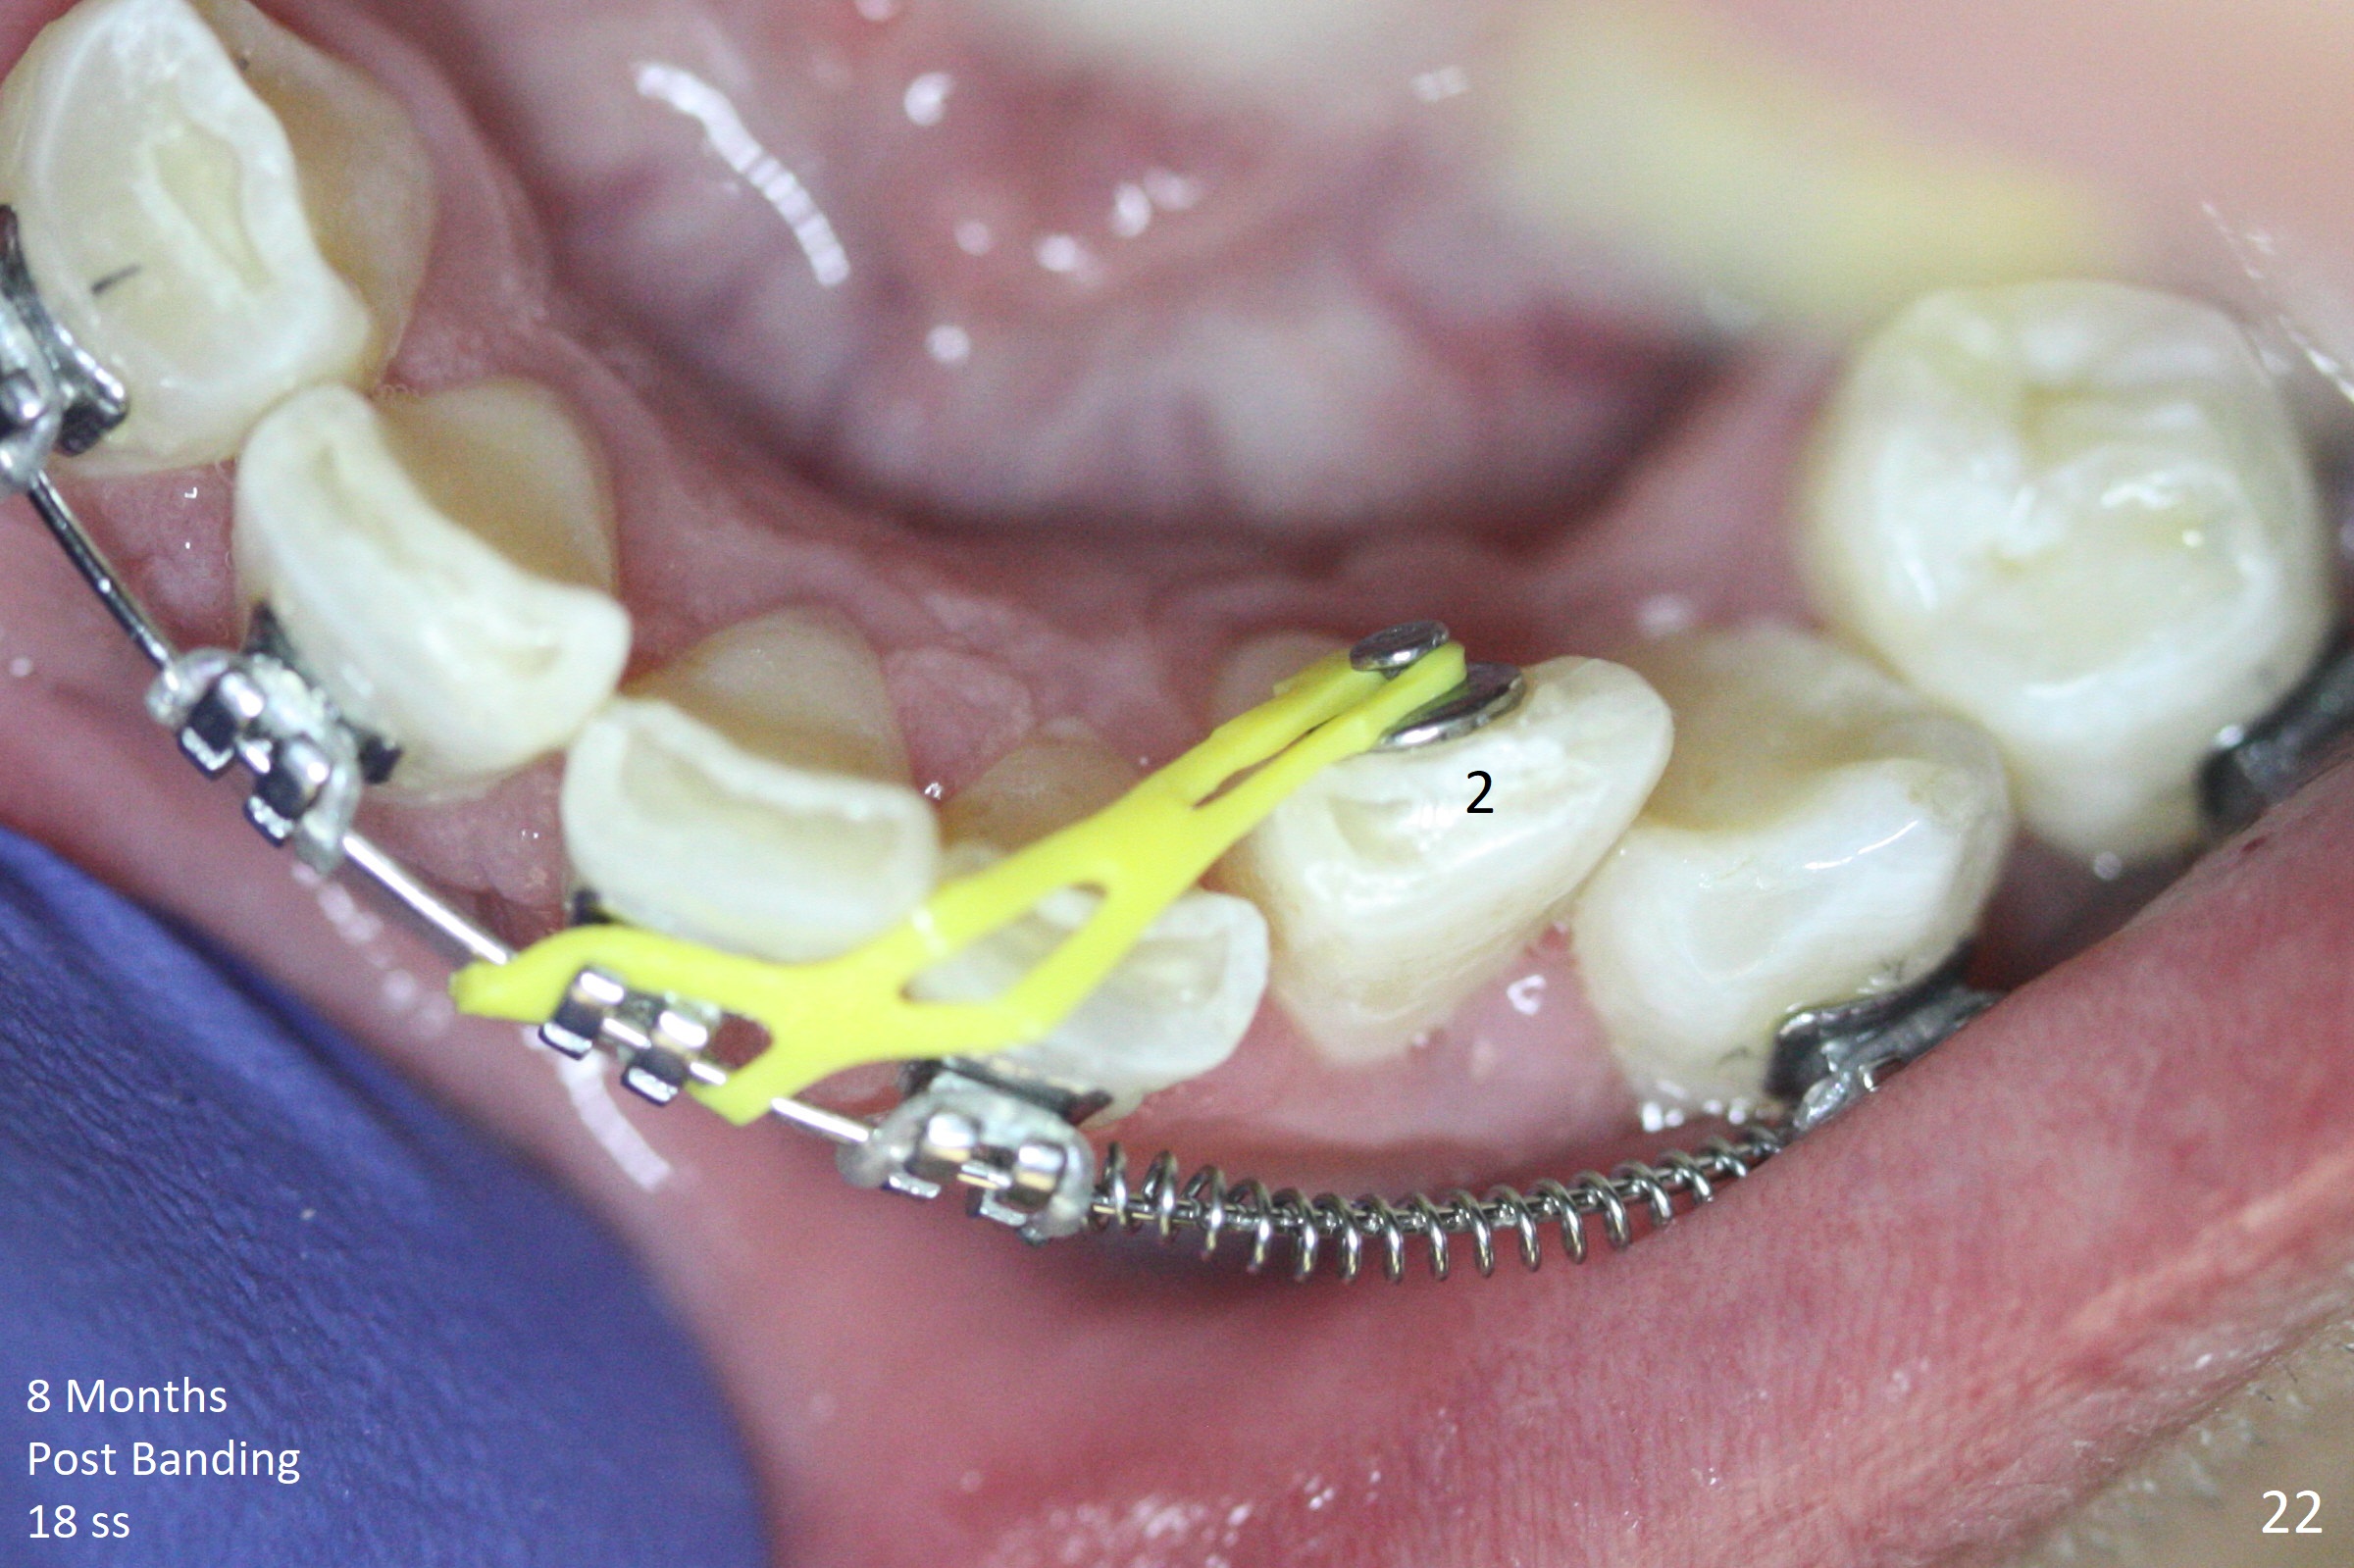

Severe crowding (Fig.1-7) appears to be alleviated especially 2 months after UR5 extraction. Diastemata seem to form mesial and distal to UR2 (Fig.8). Because of severe wear at UR3 (Fig.6), there is no bracket placement differential around it (Fig.8 (14 niti wire)). Lower bands and brackets are placed a week later (Fig.9-11). Because of tight space between LR4 and the opposing tooth (Fig.10), band adhesive is applied to L7 occlusal surface to open the bite (Fig.9). There is an abrupt kink of 12 niti wire between LL4 and 6 (Fig.11). The latter does not improve much in a month; the wires remain the same (Fig.12). For LL2, LR4 has been retracted for ~ 1 month (Fig.13). There is mild tension when 18 ss wire is inserted between LL4 and 6 five point five months post banding (Fig.14). UR4 has been distalized for a month using buccal power chains x3 resulting in rotation; to counter the rotation, a lingual button is placed with power chain x3 lingual and x2 buccal (Fig.15). With space gaining, it is time to finish definitive filling (Fig.16 *). Next visit check midlines, overjet, interdigitation, and molar classification. R4s distalize, but associate with rotation because of power chains buccal and lingual 8 months post banding (Fig.17,18). With the use of the same wires, power chains are applied lingual to continue distalization and rotation correction (Fig.20,21). Lingual buttons are placed at L2s buccalization (Fig.19) and mesialization (Fig.22,23). It appears that space should be created distal to LR3. That is that the lower anterior teeth should be shifted to the right, although it may be not appropriate for the midline.